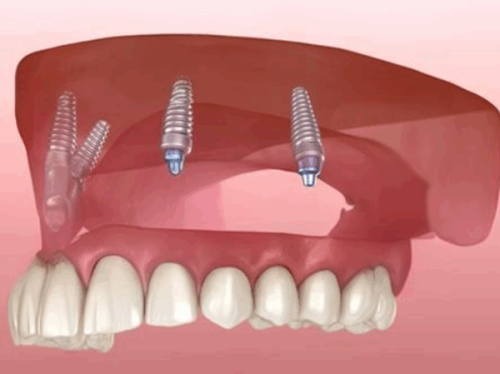

康斯坦丁医生深耕口腔种植及修复领域多年,技术扎实全面,拥有深厚的德国口腔诊疗技术背景,不仅是德国Ankylos种植系统培训师、德国SDS种植体研发医生团成员,还参与德国FORESTADENT非凡正畸专项技术研发。他耐心细致,擅长和患者沟通,能根据患者口腔情况制定个性化诊疗方案,具备处理各类复杂口腔种植病例的能力,还能将国际先进的种植技术与国内患者口腔实际情况相结合,优化诊疗方案,提升治疗效果与患者体验,多年来深受患者喜爱,行业认可度颇高。